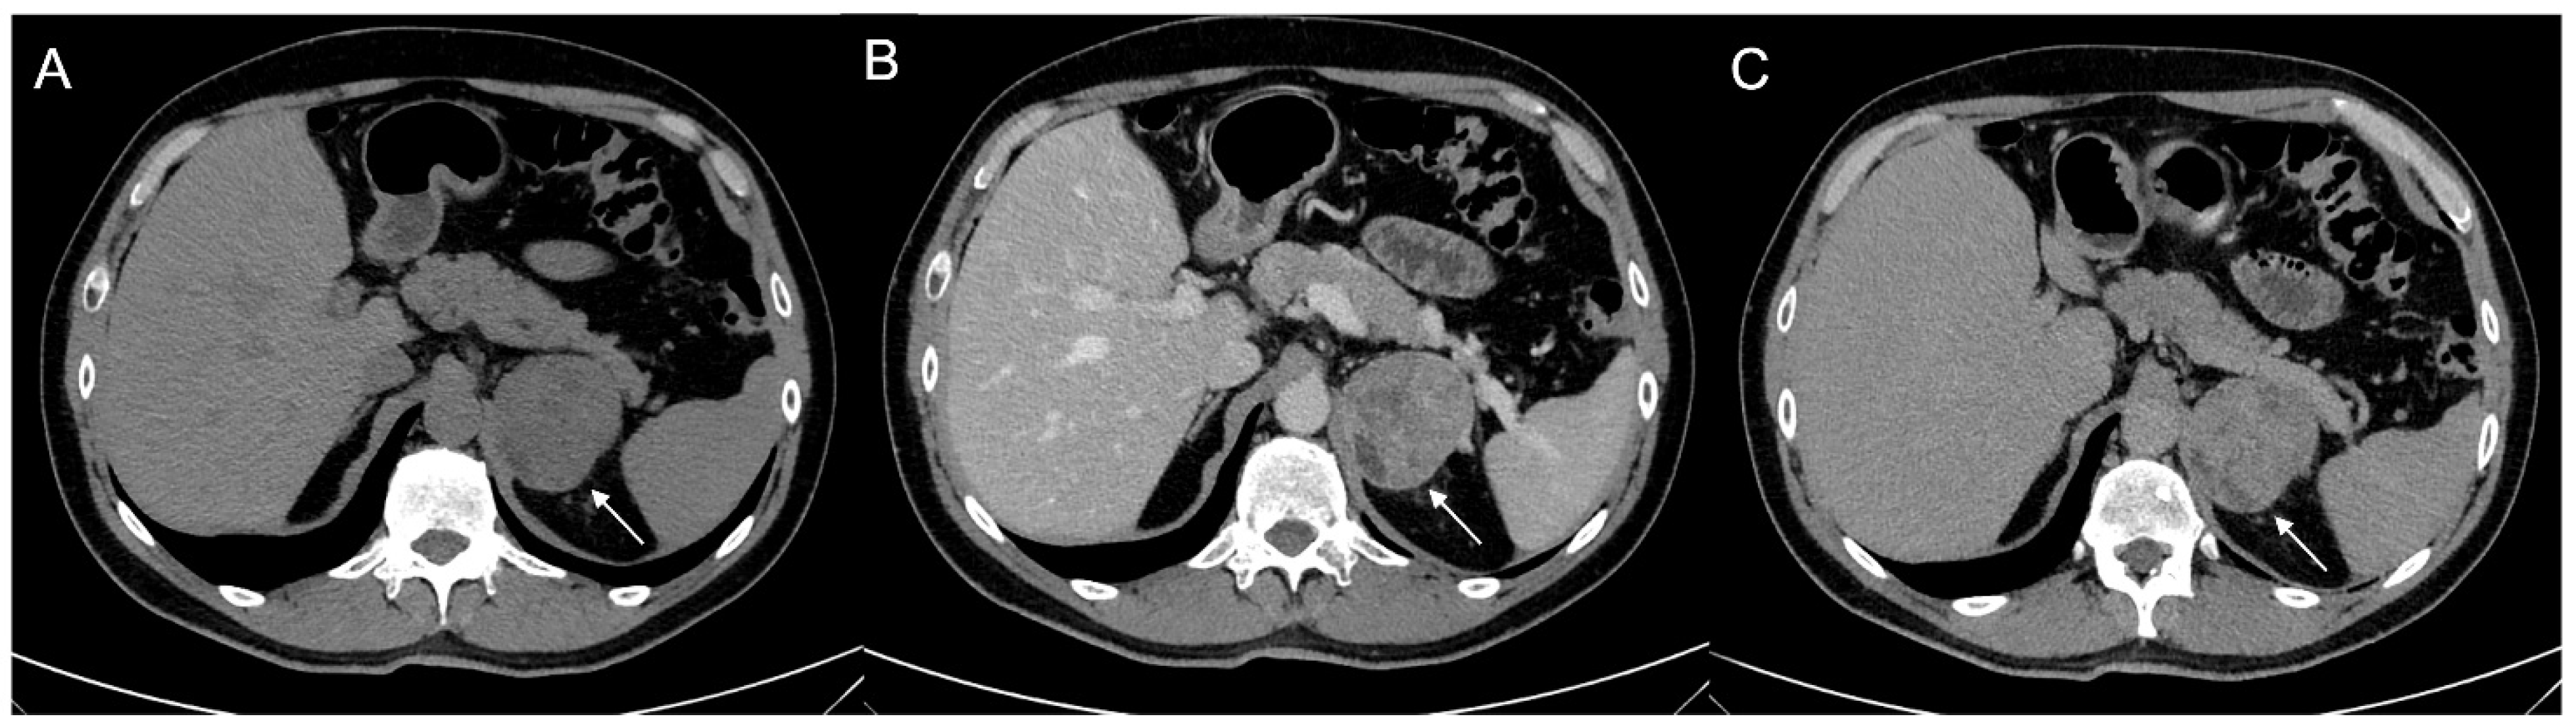

Figure 9.

Voluminous lesion (arrow) of the left adrenal gland measuring 60 × 55 mm with density value > 20 HU on basal CT (A) and inhomogeneous enhancement on venous (B) and late post-contrast phases (C) due to the presence of necrotic and cystic areas. Histological diagnosis of Adrenocortical carcinoma.

Figure 10.

Man 60 years old with left adrenal incidentaloma. Hypodense mass (arrow) without contrast enhancement on CT (A,B), typically benign, stable in follow-up.